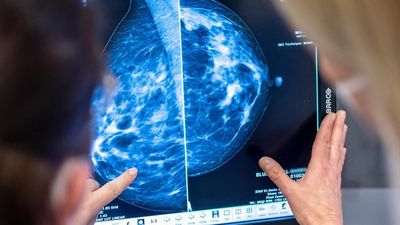

Afërsisht gjysma e të gjitha rasteve të reja përfshinin prostatën (79,600), gjirin (75,900), mushkëritë (58,300) ose zorrën e trashë dhe rektumin (55,300).